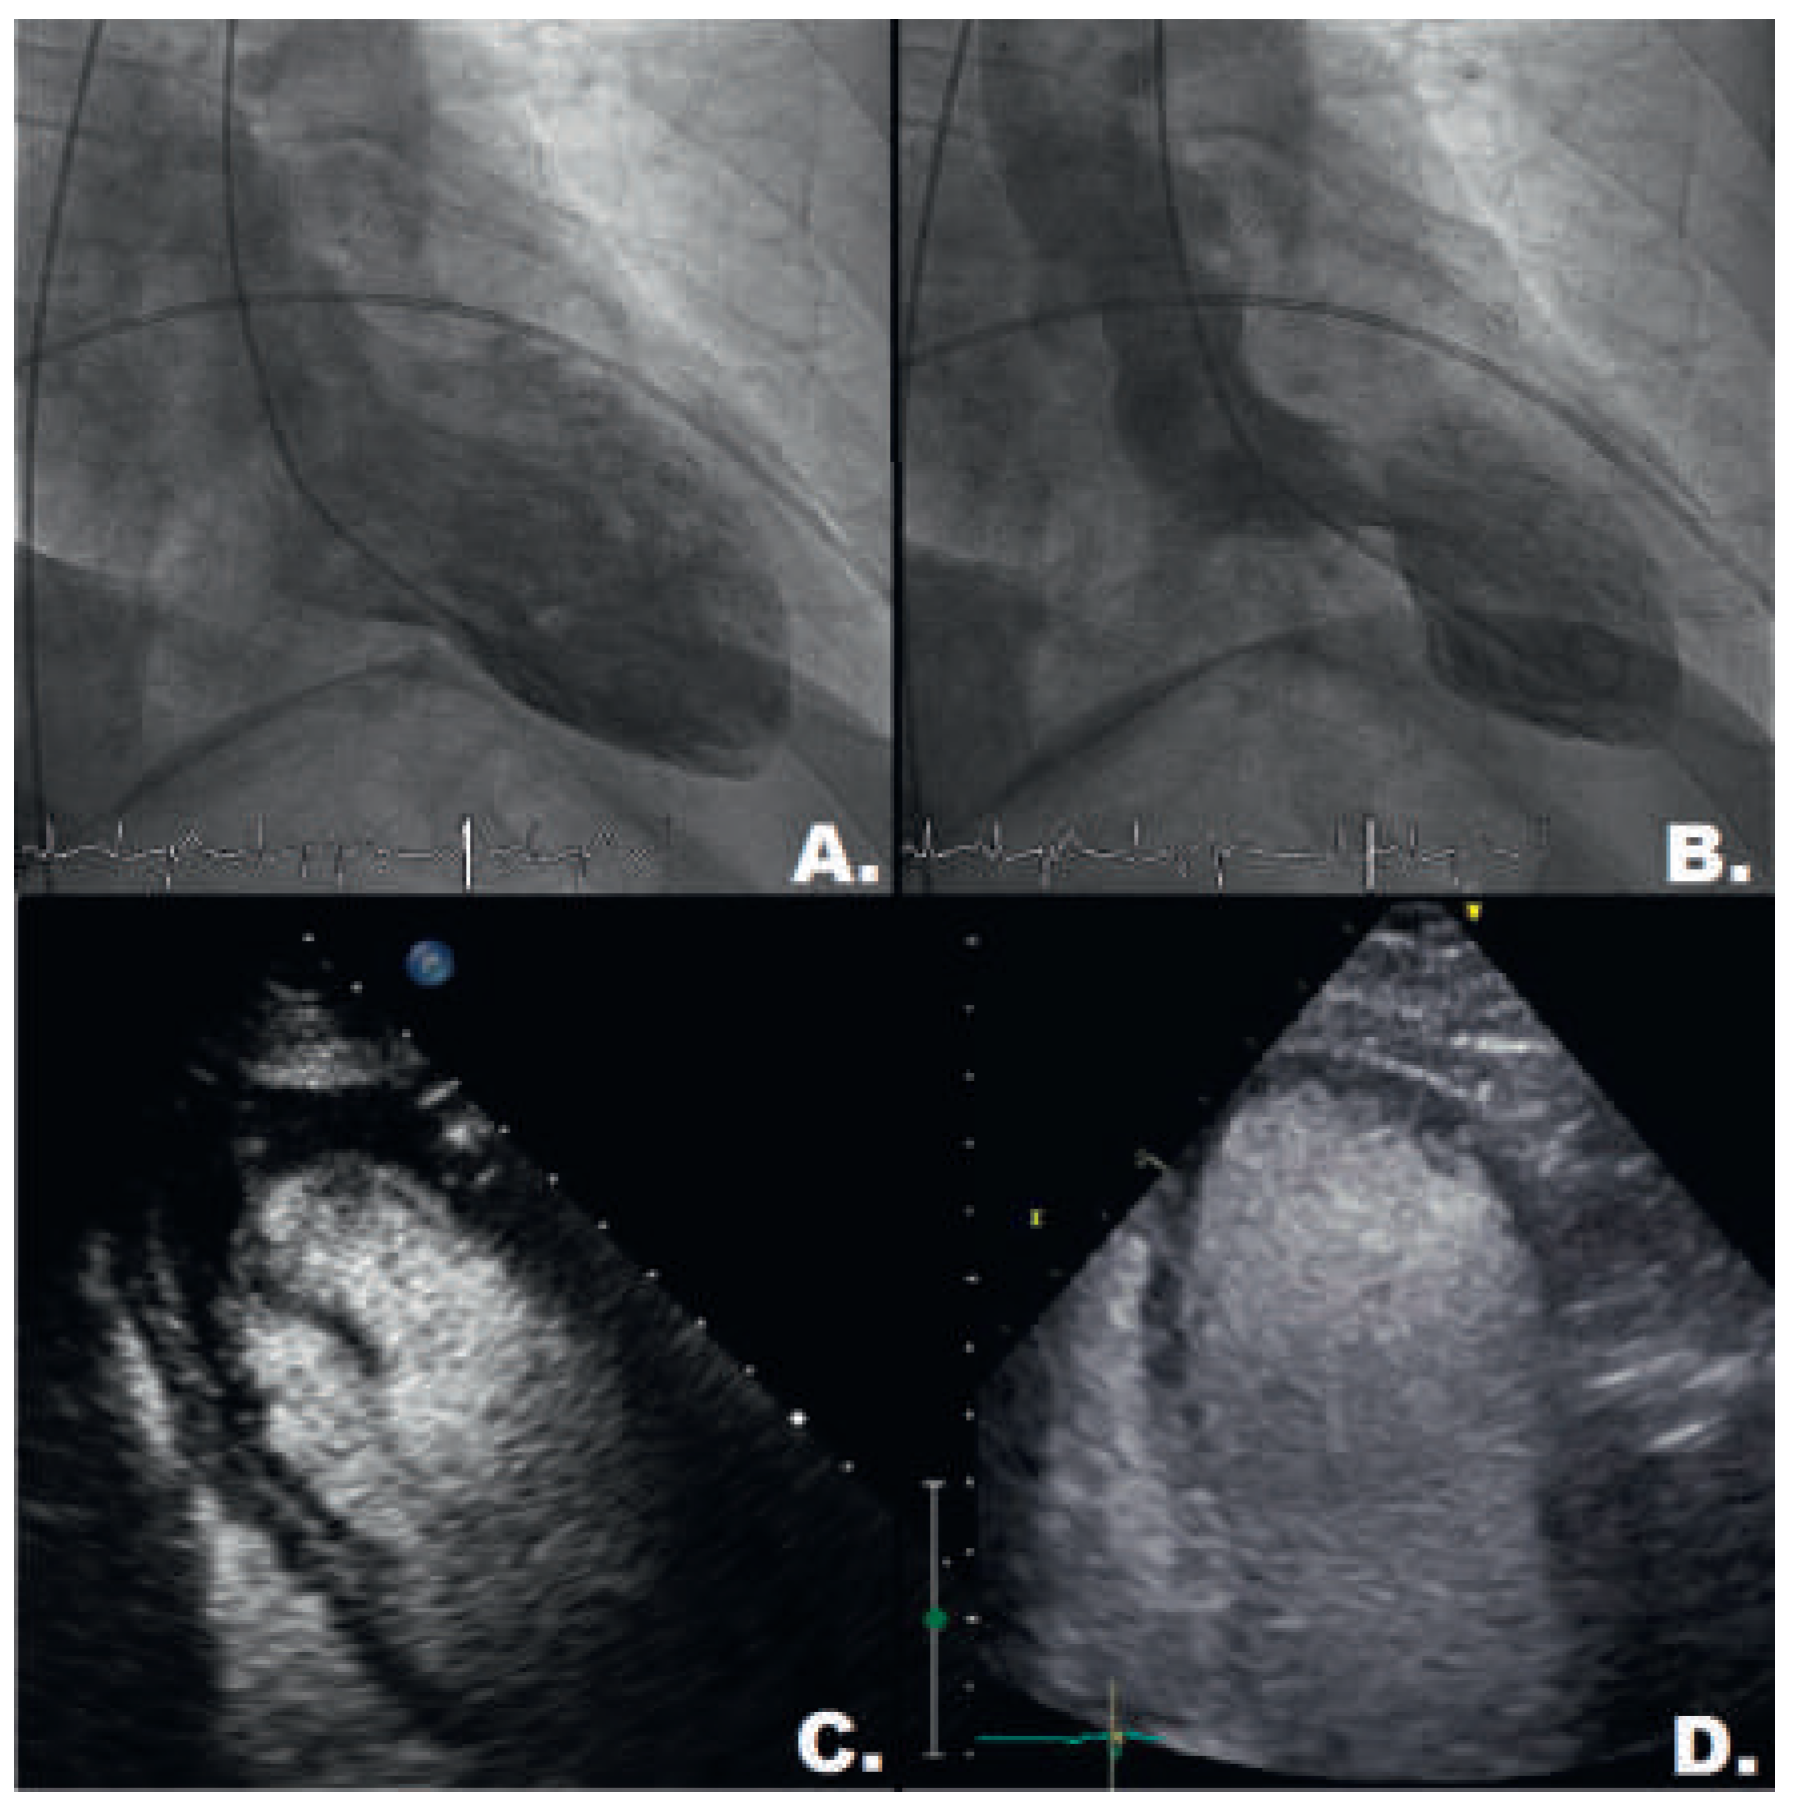

Case description